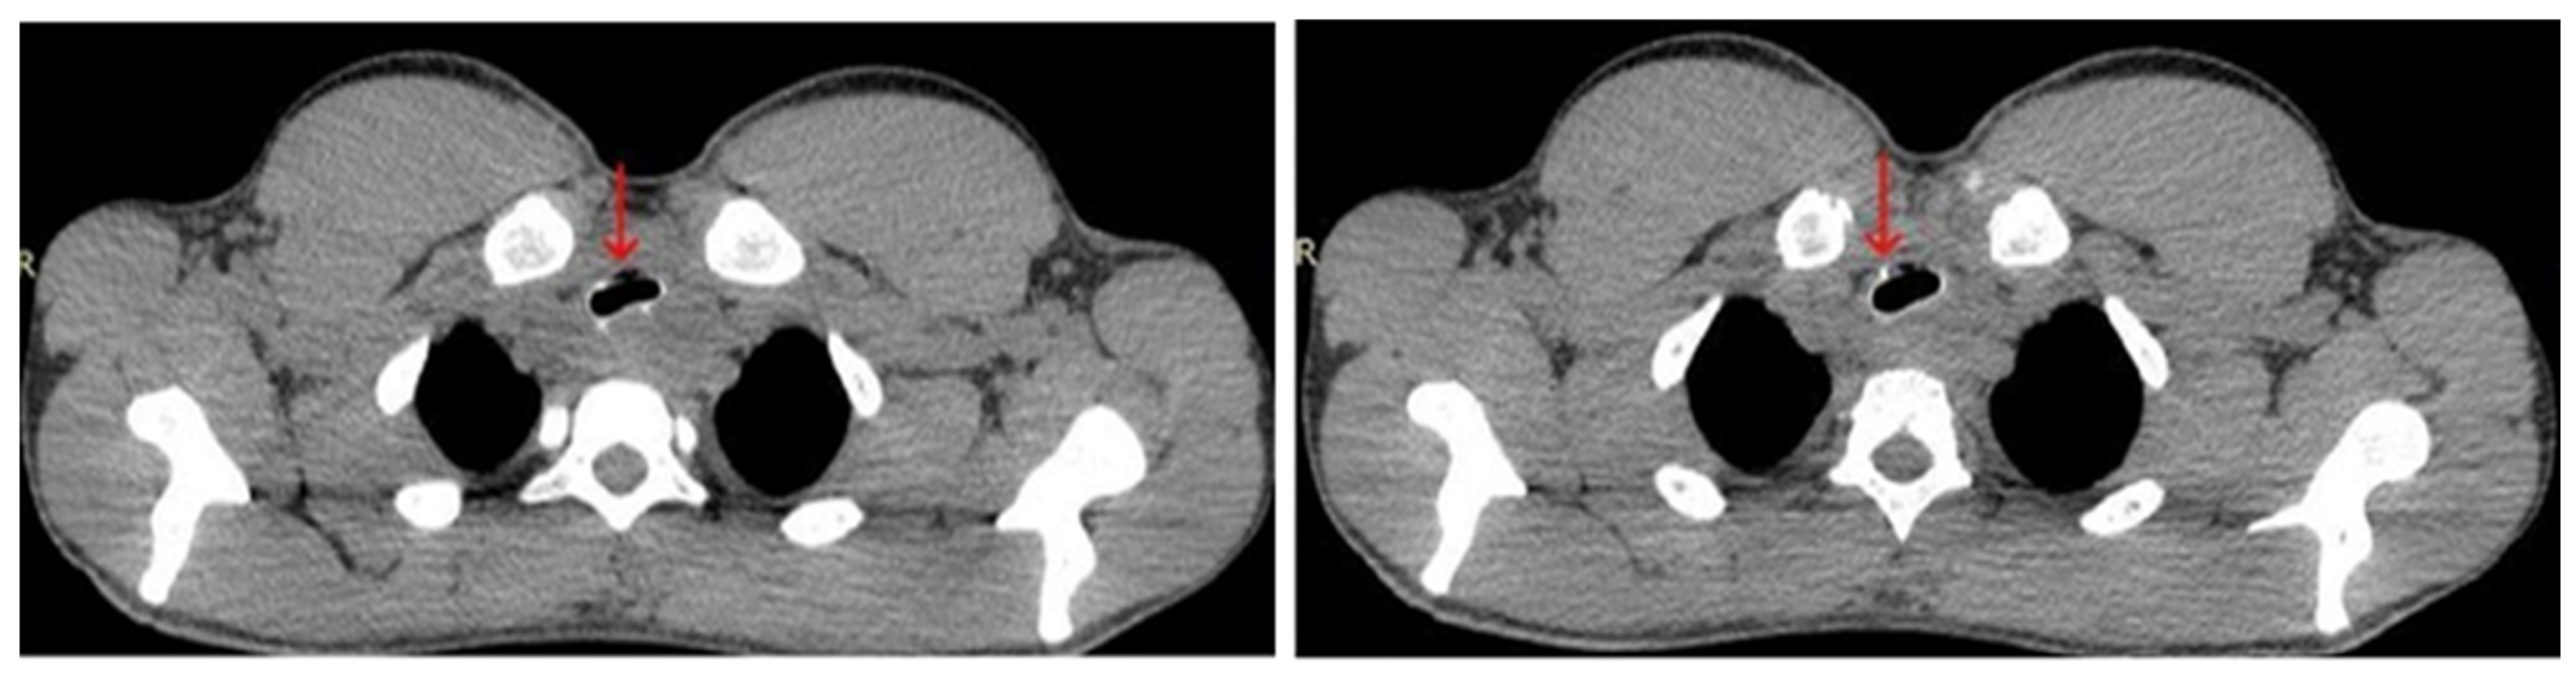

2. Case Report